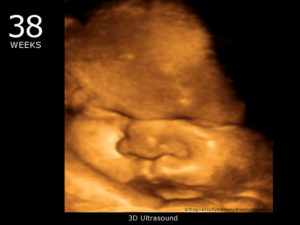

На 38 недели плановое УЗИ назначается редко. В таком возрасте уже прекрасно видно ребенка, можно разглядеть черты его лица. Врач, проводя обследование на этом сроке, оценивает состояние плаценты, расположение плода и пуповины, подсчитывает сердечные сокращения.

Фото плода

Предлагаем вам напоследок посмотреть фото плода на 38 неделе беременности.